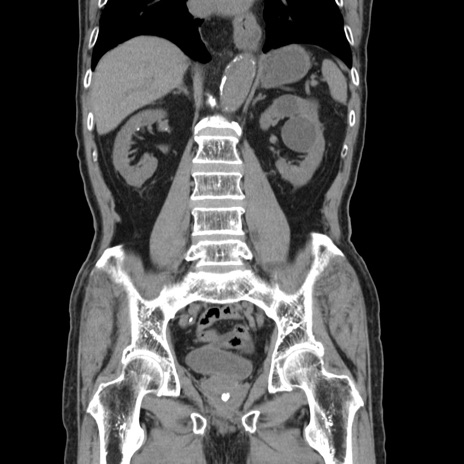

症例24(冠状断像)

【症例】80歳代男性

【主訴】左側腹部痛、嘔吐

【現病歴】本日早朝より左腹部に痛みあり。昼頃嘔吐認めたため、救急要請。

【既往歴】直腸癌(Mile手術)、胆摘

【身体所見】意識清明、BT 35.9℃、BP 221/93mmHg、SpO2 97%(RA) 、腹部:左ストーマ周囲に限局性の腹部膨隆あり。 膨隆部自発痛・圧痛あり・軟。

【データ】WBC 7700、CRP 0.09